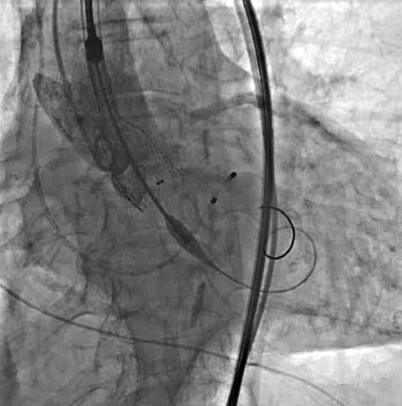

瓣膜定位及释放:将VenusA-Pro 23mm型号瓣膜系统送至主动脉瓣口处,以定位模式行造影,定位满意后释放瓣膜至工作位后,行定位造影,观察瓣膜位置及冠脉血流情况。瓣膜位置满意后完全释放瓣膜。

术后造影:以升主动脉模式造影显示瓣膜工作良好,少量瓣周漏,冠脉未受影响。术后测跨瓣压差5mmHg,主动脉瓣口峰值流速186cm/s。